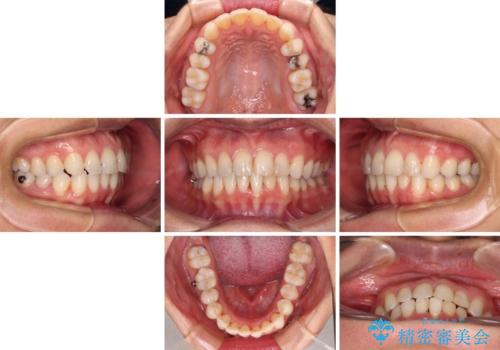

- 1年1ヶ月

下顎善の叢生をもう少し改善したかったのですが、患者様は十分に整ったとのことで治療を終えることになりました。